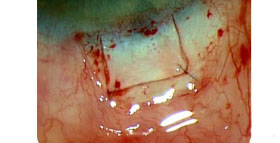

Trabeculectomia